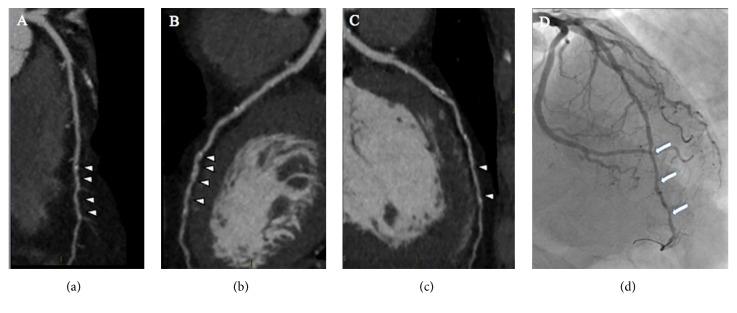

Coronary stenosis severity is both a powerful and a still debated predictor of prognosis in coronary artery disease. Coronary computed tomographic angiography (CCTA) has emerged as a noninvasive technique that enables anatomic visualization of coronary artery disease (CAD). CCTA with newer applications, plaque characterization and physiologic/functional evaluation, allows a comprehensive diagnostic and prognostic assessment of otherwise low-intermediate subjects for primary prevention. CCTA measures the overall plaque burden, differentiates plaque subtypes, and identifies high-risk plaque with good reproducibility. Research in this field may also advance towards an era of personalized risk prediction and individualized medical therapy. It has been demonstrated that statins may delay plaque progression and change some plaque features. The potential effects on plaque modifications induced by other medical therapies have also been investigated. Although it is not currently possible to recommend routinely serial scans to monitor the therapeutic efficacy of medical interventions, the plaque modulation, as a part of risk modification, appears a feasible strategy. In this review we summarize the current evidence regarding vulnerable plaque and effects of lipid lowering therapy on morphological features of CAD. We also discuss the potential ability of CCTA to characterize coronary atherosclerosis, stratify prognosis of asymptomatic subjects, and guide medical therapy.